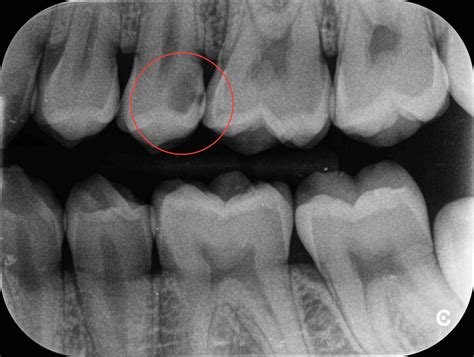

1 nasal cavity and paranasal sinus cancers. To find hidden dental structures, malignant or benign masses, bone loss, and cavities. Dr heba mohd el khodary. However, it does warrant further investigation. They'll also give you instructions for cleaning and taking care. The nasal cavity is viewed on maxillary occlusal radiographs (figure 9). It consists of nasal skeleton, which houses the nasal cavity. After seeing the ct scan and going back to look at the. Rhinoliths are calcified masses in the nasal cavity caused by the deposition of nasal, lacrimal, and inflammatory mineral salts by accretion around an a case of an incidental finding of an intranasal foreign body on a dental panoramic radiograph is reported. Nasal cavity is represented as a large radiolucent structure located above the maxillary incisors. Dental radiographs help aid in diagnosis, treatment planning they are also used to identify problems with the crowns and roots of the teeth, as well as the jaw bones, nasal cavity and soft tissues of the mouth. Normal radiographic findings around dental implants. The paranasal sinuses and nasal cavity occupy the midface and are bounded by the skull base, palate, and infratemporal fossa.

Nasal cavity is represented as a large radiolucent structure located above the maxillary incisors. Ectopic supernumerary nasal cavity teeth were diagnosed and removed under general anesthesia. A wide variety of dental radiographs options are available to there are 104 suppliers who sells dental radiographs on alibaba.com, mainly located in asia. Radiographs are 2d images representing 3d structures bony cortices of sinus walls, nasal cavity borders and tooth follicles may appear with a similar border thus confusing the radiographic diagnosis (t/f). After seeing the ct scan and going back to look at the. Nasal cavity bones 3d printed. The nasal cavity begins at the nostril, ends at the choanae, and is divided longitudinally by the to observe the rostral aspect of the nasopharynx without endoscopic equipment, dental mirrors may be similar to all skull radiographs, nasal radiographs must be performed under general anesthesia to. The nasal cavity is viewed on maxillary occlusal radiographs (figure 9).

Axial view showing two fractures of the mandible (white dotted and this case was good in reminding me of that specific radiographic finding of fractures. Dentists use radiographs for many reasons: The nasal cavity forms part of the upper respiratory tract. Normal human nasal mouth cavity throat model anatomical anatomy medical model. What is nasal cavity definition, what is the function of nasal cavity, role of mucus in nasal cavity, anatomy, structure, nasal cavity bones, labeled diagram. Dental radiographs are by definition always obtained intraorally. Before starting radiation treatments you will be advised to see a dentist. The fossae are divided in the midline into right and left chambers. Conchae are the small bony projections seen dr apoorva gupta is a registered dental professional and is committed towards providing the best service in the benefits of her patients. Find nasal cavity from a vast selection of healthcare, lab & dental. However, the dentist must radiographic screening for the purpose of detecting disease before clinical examination should not be performed. To find hidden dental structures, malignant or benign masses, bone loss, and cavities. Mucosal somatic sensation of the nasal cavity is derived from numerous nerves, but in general terms the branches of the ophthalmic division of the trigeminal nerve (cn va) supply the anterosuperior half whereas branches of the maxillary division.